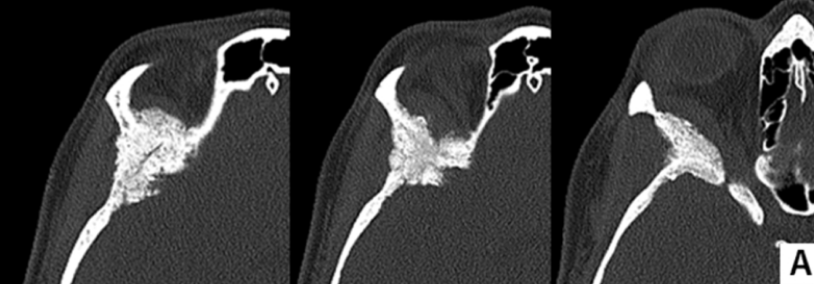

术前计算机断层扫描(骨窗)显示蝶骨大翼、蝶骨小翼、前床突及眼眶上壁、颞骨鳞部存在增生性改变。增强MRI检查可见蝶眶脑膜瘤从眶上壁延伸至外侧眶壁及眶周区域,颞极硬膜和颞肌受浸润,眼眶受压导致眼球突出征象。